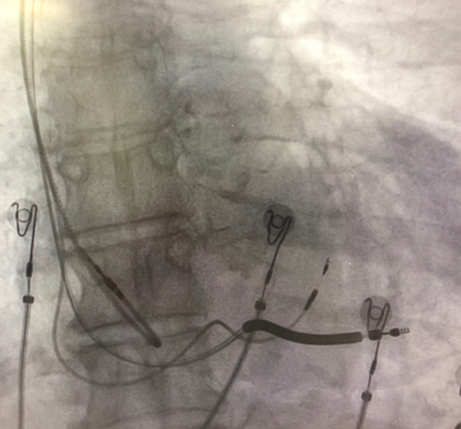

由于明确患者没有合适的靶静脉,薛玉梅主任果断更换手术策略,改行左束支起搏代替左室电极,电极精准放置于左束支区域,起搏图形呈典型左束支起搏,高低电压(1V及5V)达峰时间均为75ms,确定为选择性左束支起搏。起搏阈值仅为0.7V/0.4ms,效果良好;随后心房电极及右室除颤电极均顺利植入,参数良好,在连接好机器后,完美结束手术。

术后不同体位下影像

术中手术过程